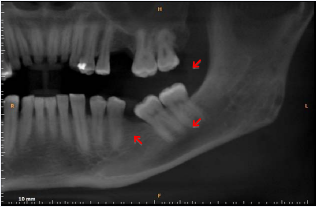

About 30% of the patients with multiple myeloma have bone lesions in the jaws [10]. These lesions are more frequent in the posterior area of the lower jaw, mainly in the ramus, angle, body and coronoid process [2,3,8,11,12]. The upper jaw is rarely affected, and when this happens, it is usually in the tuberosity region [16]. There is no consensus on the main radiographic aspects of bone lesions affecting the jaws of patients with multiple myeloma. Different radiographic aspects have been described, however the most common aspect is the “punched out” lesion (Figure 1), which may be presented as single or multiple osteolytic bone lesions, or even as diffuse and not bounded [12,18].

Figure 1: Cone Beam Computed Tomography, panoramic slice showing multiple uni locular hypondense lesions, with well-defined margins characterized by “punched-out” lesions in the left mandibular angle and ramus.